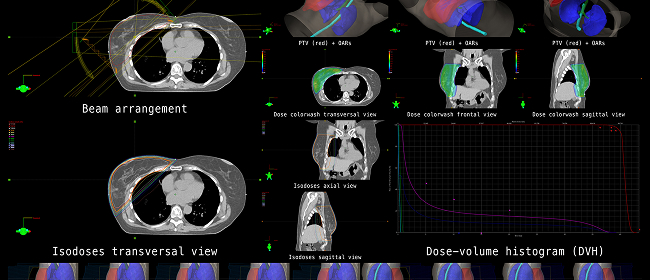

Radioterapia de Intensidad Modulada (IMRT)

Administra radiación con precisión, moldeando la dosis para adaptarse al tumor.

Radioterapia Guiada por Imagen (IGRT)

Utiliza imágenes en tiempo real para mejorar la precisión durante el tratamiento.

Radioterapia 3D Conformal

Personaliza la entrega de radiación según la forma y ubicación del tumor.

Radioterapia Estereotáxica Corporal (SBRT)

Proporciona radiación de alta dosis en menos sesiones, ideal para ciertos tumores en etapa temprana o bien definidos.

Nuestro centro cuenta con el Sistema Accuray TomoTherapy®, una plataforma avanzada que combina imágenes por TAC y la administración de radiación en un sistema integrado. Esto permite:

- Administración continua de radiación de 360 grados

- Precisión sincronizada en la focalización de las dosis

- Reducción de la exposición al tejido sano circundante